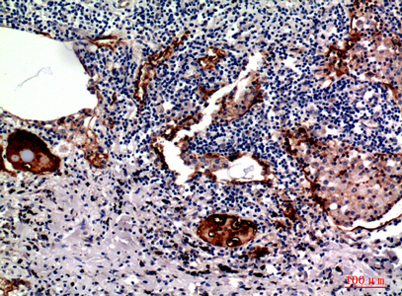

Product name: Mucin 1 rabbit pAb

Dilutions: Western Blot: 1/500 - 1/2000. IHC-p: 1:100-1:300. ELISA: 1/10000. Not yet tested in other applications.

Immunogen: The antiserum was produced against synthesized peptide derived from the Internal region of human MUC1. AA range:1021-1070